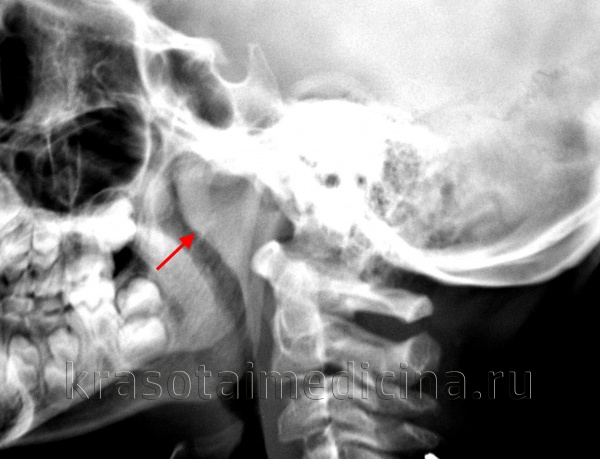

- Рентгенография носоглотки. Применяется при наличии клинических признаков сопутствующей гипертрофии глоточных миндалин и низкой информативности задней риноскопии. Позволяет определить степень обтурации просвета носоглотки лимфоидной тканью и выработать тактику дальнейшего лечения.